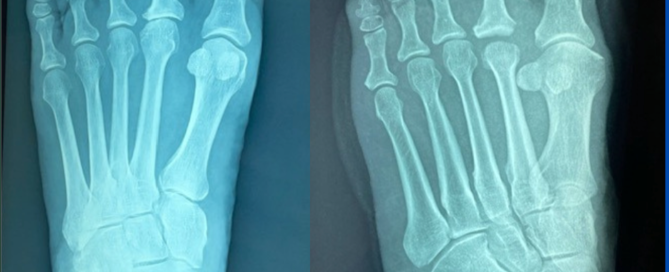

Blog's main page This was a very symptomatic 2nd MTPJ that had progressed for many years. Conservative care has been exhausted, and the patient was referred for a surgical consultation. [...]